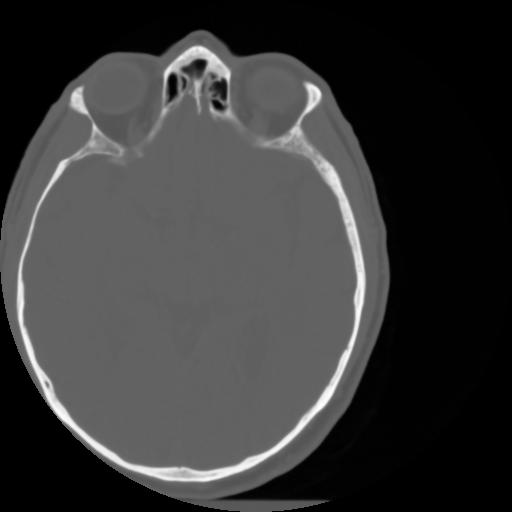

3 CEREBRO,,Axial,3.0,CEREBRO,,